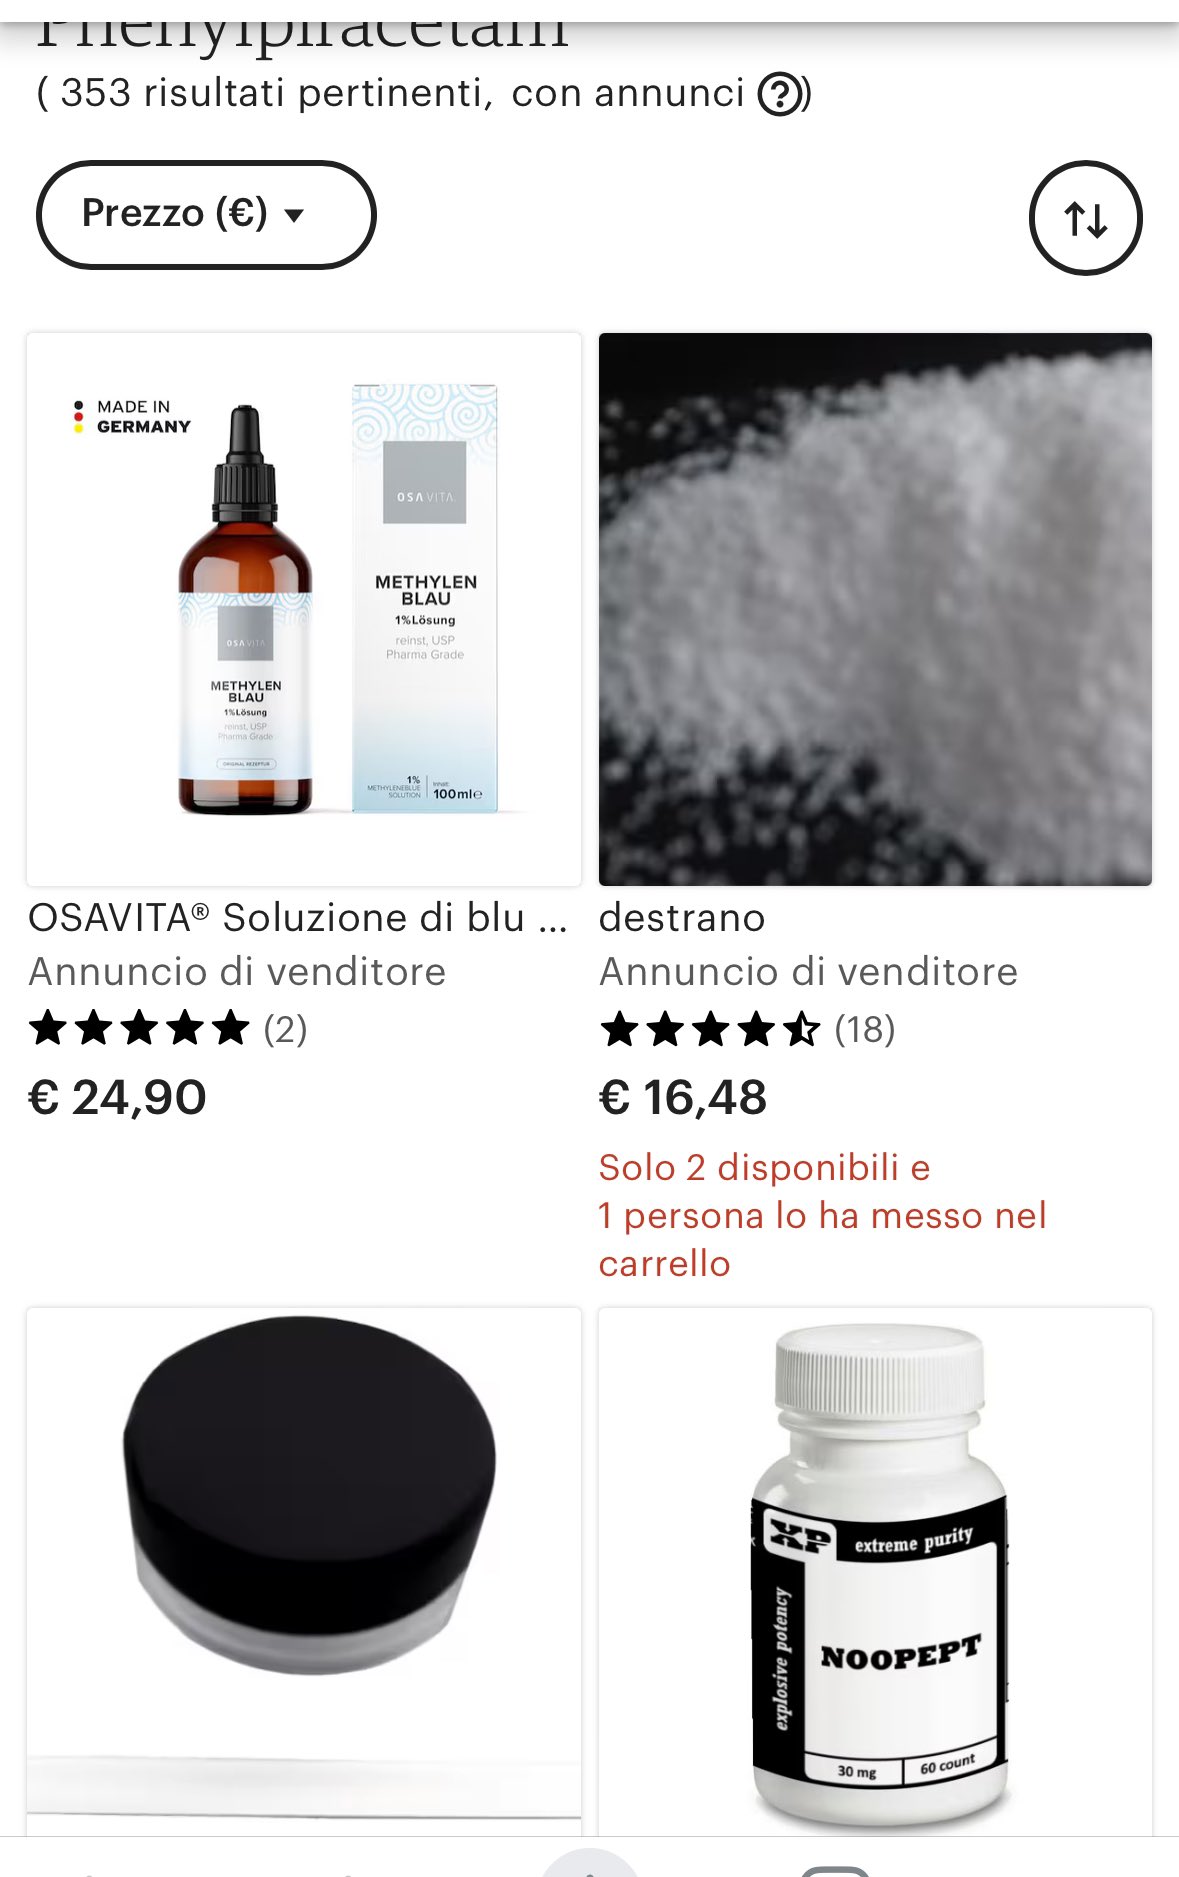

首先,从定义上讲,“反解离(anti-dissociative)”并不是一个标准的医学术语或者广泛认同的药理学分类。在正规资料,比如医学文献、维基百科、精神药理学教科书中,目前并没有“反解离药物”这个正式概念。

看上去像是为了描述某类特定效应而创造的术语(可能是nmda受体活性增强),用来对抗因NMDA受体拮抗剂(比如氯胺酮、DXM、PCP等)引发的解离体验(dissociation)。

那么更常见的是将其归入认知增强剂(cognitive enhancers),特别是改善认知连接性(connectivity)和现实感知(reality testing)的类型。

但其实在药理学上,单纯用“受体激动剂”来逆转“受体拮抗剂”的效应,有时会导致过度激活。

对于NMDA受体而言,过强的NMDA活化本身就与兴奋性毒性(excitotoxicity)和精神病样症状(psychotomimetic effects)有关,比如谷氨酸风暴可以引发严重的焦虑、妄想、乃至癫痫。

也就是说,简单地“激动-解除拮抗”在中枢神经系统是很危险的做法,尤其是对于易感个体(如有精神分裂素质的人)。

科学的处理方式一般是通过更细致的调节,比如微调NMDA/AMPA平衡、调节其他辅助途径(如GABA、5-HT、mGluR受体),而不是简单粗暴地用“NMDA增强剂”去顶回去。

而临床处理药物中毒中,其实医生更常用的做法是保守、支持性的治疗,比如补液,促进代谢,必要时镇静,以及监测生命体征防治并发症。

药物拮抗与受体激动之间,往往牵扯到的是复杂的适应性变化(receptor upregulation/downregulation),

不是简单的“给多一点刺激就能抵消”的关系